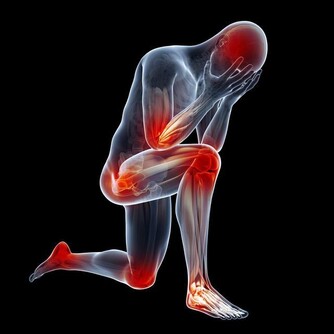

1.適當出汗

運動量要以出汗為宜,幫助排出體內蓄積的毒素。